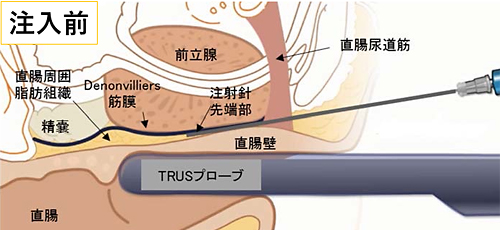

- 前立腺と直腸の間の隙間に注射針を挿入する操作を観察できるように、超音波プローブを挿入します(図:注入前)。

- 肛門開口部より2cm上部の皮膚から注射針を挿入。超音波を見ながら、直腸尿道筋を貫通し、前部直腸壁と前立腺の間の直腸周囲脂肪組織に達するように注射針を操作します。

- 注射針の位置を超音波画像で観察し、針先が直腸周囲脂肪組織の中にあることを確認し、生理食塩水を少量注入して空間を作成。その後にSpaceOAR®ハイドロゲルを前立腺と直腸壁の間(Denonvilliers筋膜 (腹膜前立腺筋膜))と直腸前壁の間)にスムーズに連続注入します(図:注入後)。